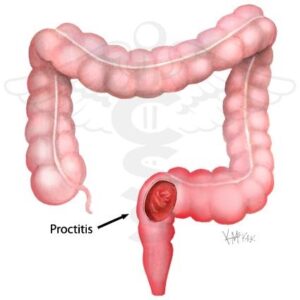

Proktit nedir

Makat kanalını da içine alan kalın bağırsağın son 15 cm’lik bölümünün iltihabı “proktit” veya “rektit” olarak adlandırılır.